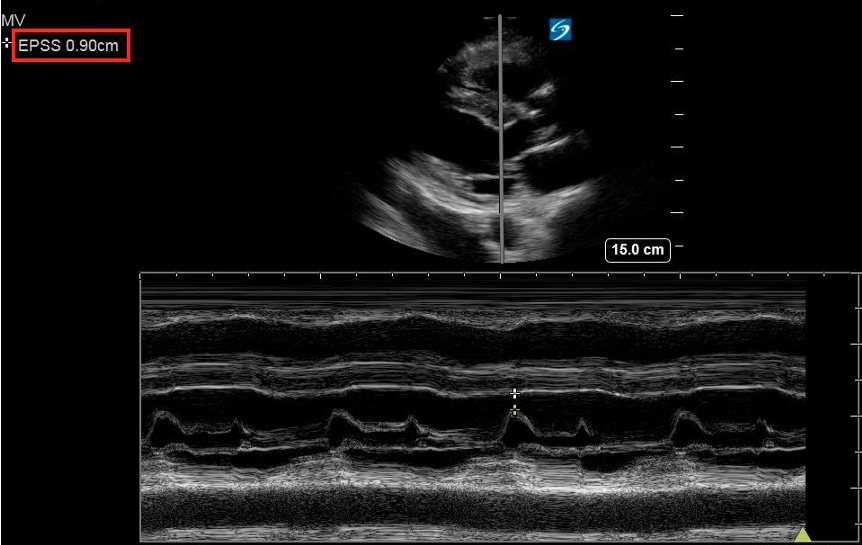

End Point Septal Separation

The EPSS is a measure of AMVL motion and is used as a way to semi-quantify LVfx. It refers to the minimal distance between the peak of the E-wave and the IVS at the same X-axis time point (figure 8).

In a normally functioning LV, the E-point comes close to the septum (figure 9). In pediatric patients, there is limited validated evidence for normal EPSS values. A 1983 study provided guidelines for the use of EPSS in infants and children and found that normal EPSS was ≤ to 6mm, with 7-8mm being tail end of normal [21]. This was confirmed in a more recent study where an EPSS of 6.17 mm optimally distinguished normal from depressed LV systolic function, with a sensitivity of 86% and specificity of 92% [12].

The larger the EPSS distance the worse the function. Similar to the AMVL visual assessment, if the E-point is not close to the IVS during the M-mode tracing, this could suggest reduced systolic function. Specific cutoff values are available to guide interpretation (table 3) (Figure 10).

Key Consideration: The EPSS should never be used as a single measure of LV systolic function as it can be influenced by many factors such as valvular dysfunction in mitral stenosis or aortic insufficiency. EPSS should always be considered in a larger evaluation of LV function including visual assessment of LV contractility. EPSS alone is insufficient to guide decisions regarding cardiology referral or formal echocardiography without corroborating functional findings.

Figure 9: PLAX M-mode with normal EPSS measurement

Figure 10: PLAX M-mode abnormal EPSS